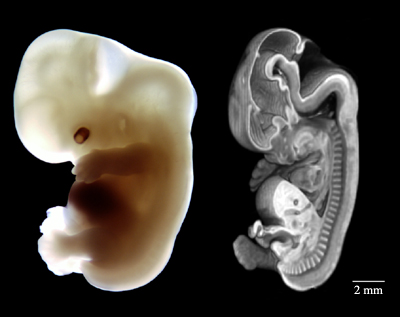

The stage of development after the chewed-like form (mudghah) is referred to as izam which means “bones” (3) and the fetus does indeed acquire a cartilaginous skeleton of bones. In the 6th week the cartilaginous skeleton begins to form and the embryo acquires a soft skeleton as we see in Figure 2.

Figure 2 and Figure 5 show a human embryo at Stage 20 (about days 50 – 51 days) showing the cartilage skeleton and skeletal musculature.(2) For further information on bone and muscle development see Embryology in the Qur’an: Bone and Muscle Development (4).

(1) The Multi-Dimensional Human Embryo, Stage 20, Day 50.

(2) Ulrich Drews, Color Atlas of Embryology, Thieme Medical Publishers, 1995. Page 98-99. Showing the cartilaginous skeleton of an embryo at stage 20 (about day 50 – 51, 18 – 22 mm).